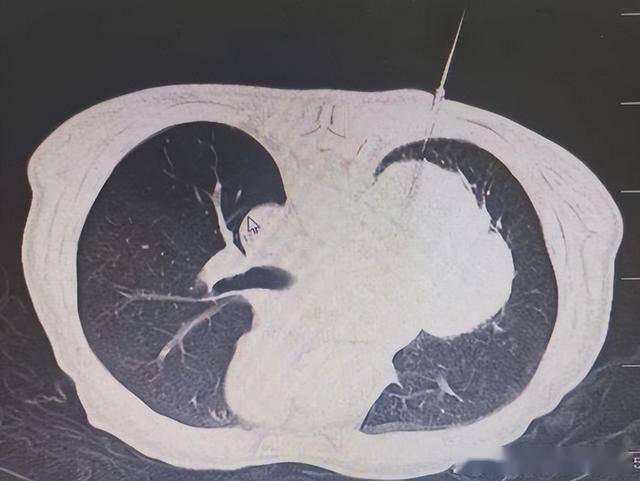

⋄ 2025年10月24日 行CT引导下经皮肺肿物穿刺活检术(微创、后续治疗方案制定的前提)。术后病理:高级别神经内分泌癌,倾向于小细胞神经内分泌癌可能。

治疗前:右主支气管完全堵塞

治疗后:右上支气管开通